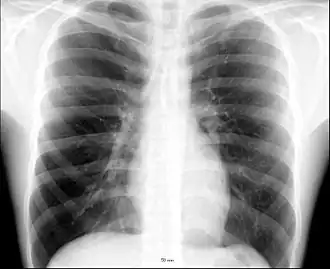

An X-ray of a human chest area, with some structures labeled

The contents of the thorax include the heart and lungs (and the thymus gland); the major and minor pectoral muscles, trapezius muscles, and neck muscle; and internal structures such as the diaphragm, the esophagus, the trachea, and a part of the sternum known as the xiphoid process. Arteries and veins are also contained – (aorta, superior vena cava, inferior vena cava and the pulmonary artery); bones (the shoulder socket containing the upper part of the humerus, the scapula, sternum, thoracic portion of the spine, collarbone, and the rib cage and floating ribs).